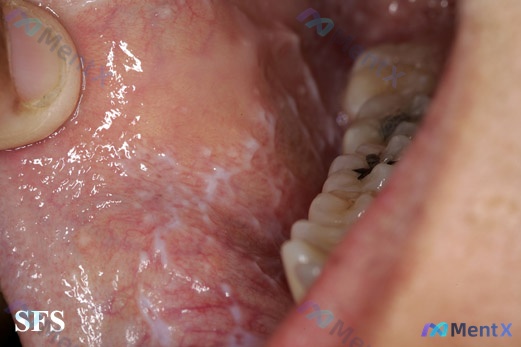

整理到一份口腔黏膜的临床影像分析资料,先抛出来给大家看看。 基本影像表现: - 部位:颊黏膜 - 核心表现:清晰的白色线状/网格状改变,交织成蕾丝状,边缘相对锐利,不可擦除 - 伴随表现:周围基准黏膜呈粉红色,有明显血管扩张纹理 - 其他:未见明显隆起性肿块、深溃疡或大面积糜烂面 这份影像资料里有几...